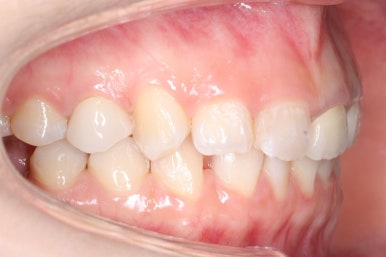

초진 때의 입안 모습입니다.

앞니는 고른 편이였으나 군데군데 틈새가 있었습니다. 약간 삐뚠 모습도 보이지만 환자분께서 개선을 하고자 했던 부분은 아래쪽 어금니 1개가 없는 자리였습니다.